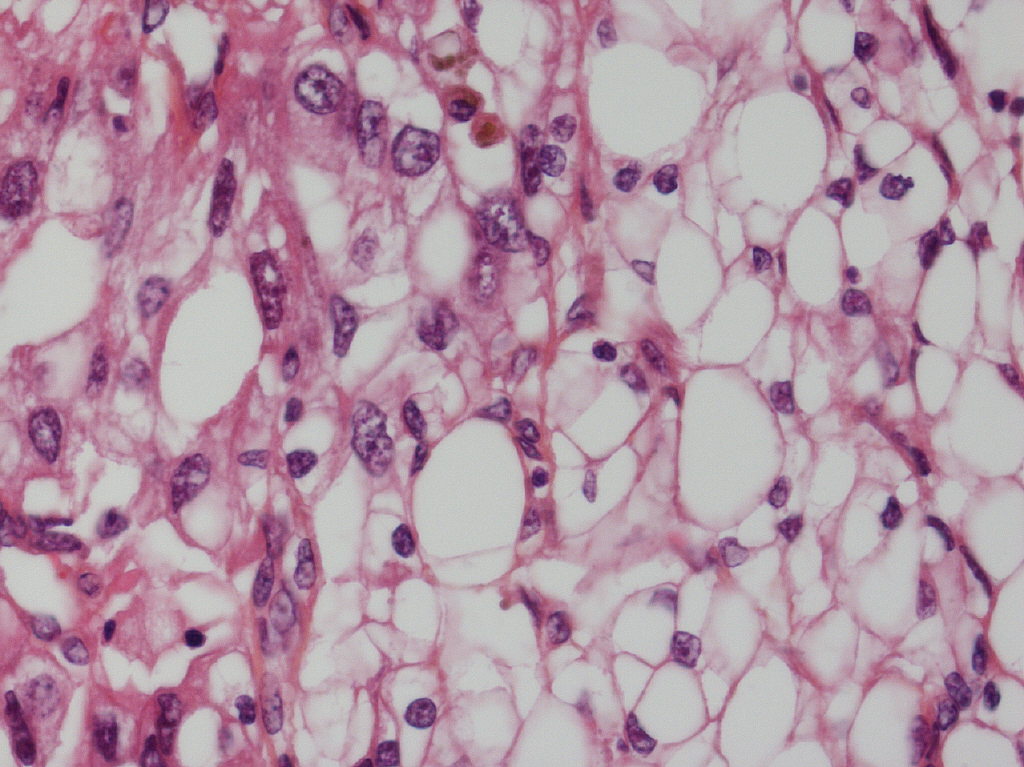

Consensus grade: WHO/ISUP grade 3

Clear cell carcinoma with different grades